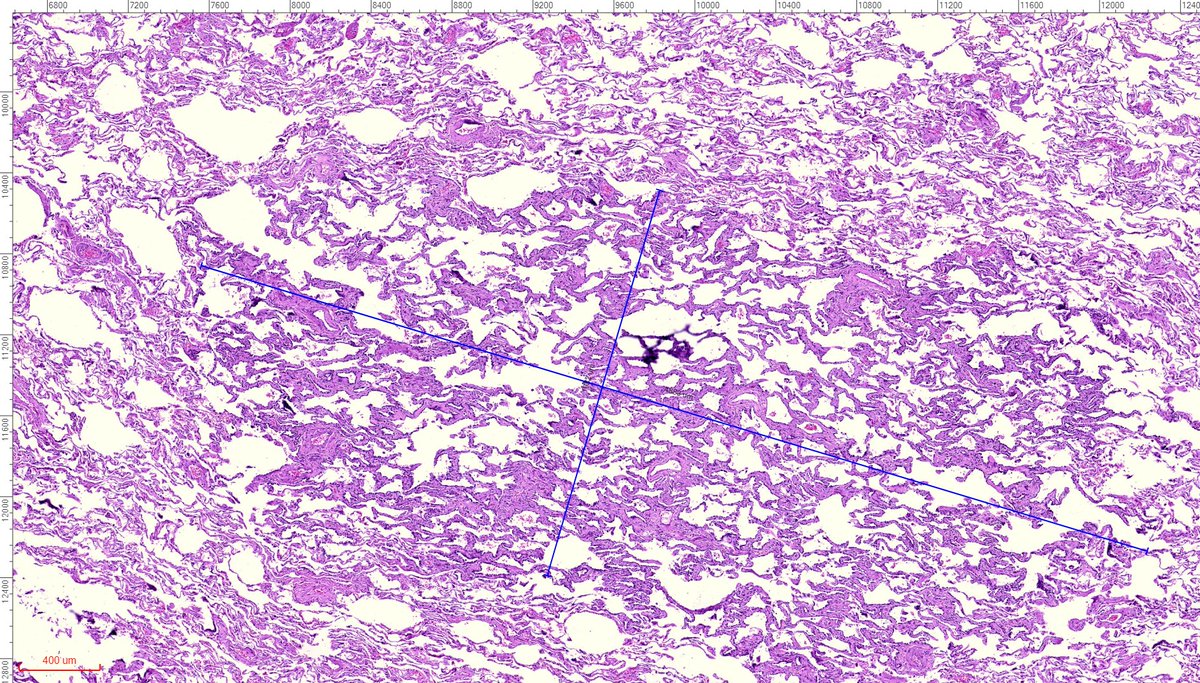

A: Lung Adenocarcinoma (in situ): Images showing emphysematous, lepidic growth pattern w/ increased presence of macrophages in the alveolar spaces, and a close-up of lepidic growing tumor cells around a blood vessel. @LungAssociation @UMRogelCancer #PulmonaryPath #DailyDX